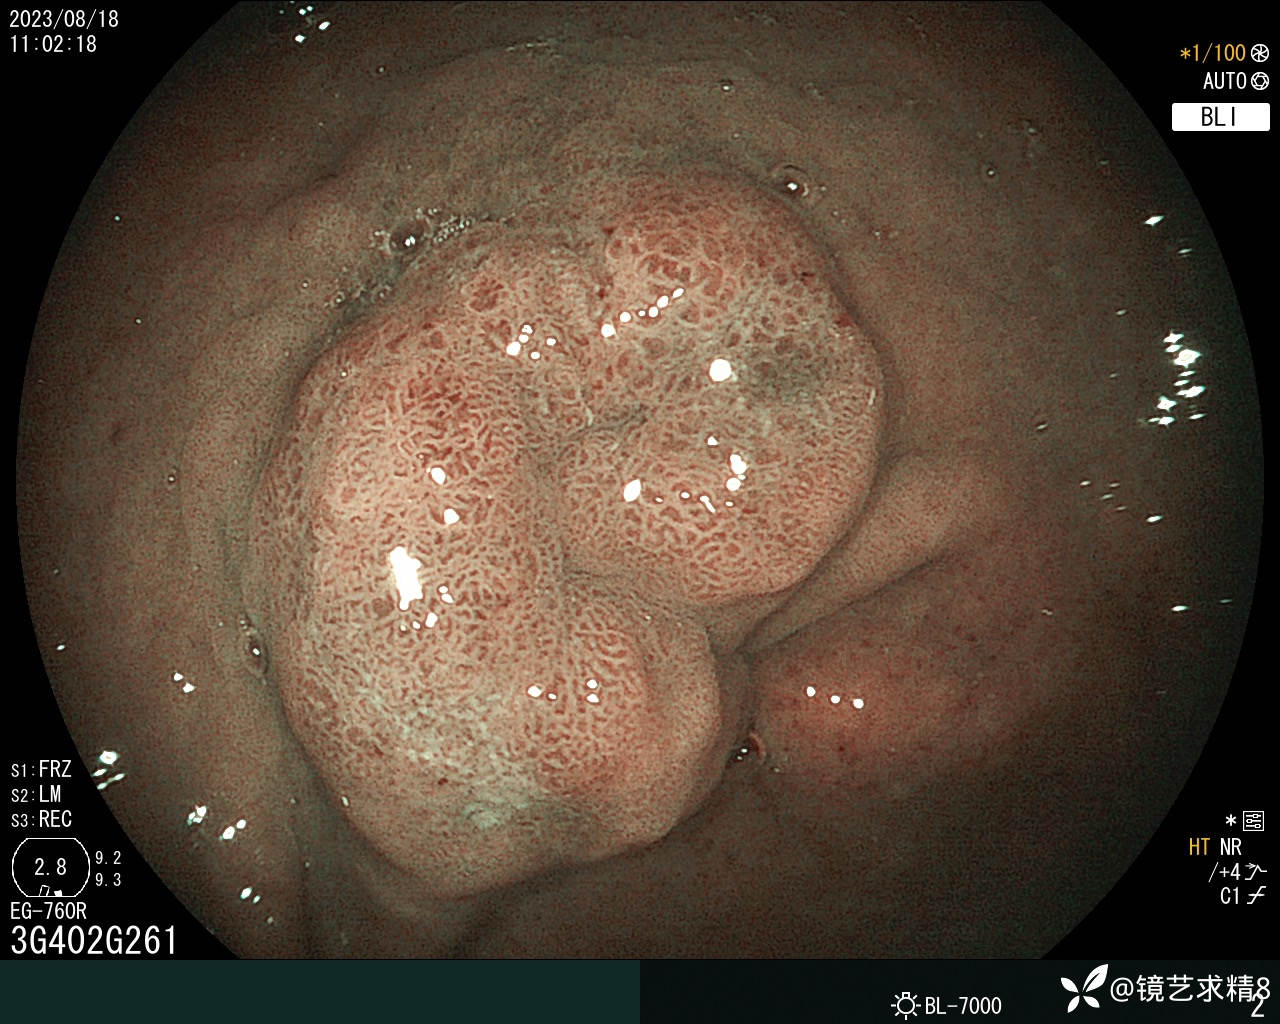

根除后予以放大镜检查如下:

病理提示:这个看上去较上次胃镜炎症明显消退很多,病变扁平化,背景色不明显,边界也不是很明显,表面看到结构还算规则,病检提示如下: